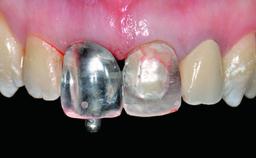

Replacement of an Upper Right Central Incisor with a Root Fracture, Early Placement of an RC Bone Level Implant, Variobase Abutment

A healthy 28-year-old female patient presented for a consultation on treatment options to restore her upper right central incisor. At the clinical examination, the tooth responded to percussion and palpation. The gingiva was red and slightly swollen, with a mid-facial probing depth of 10 mm. The upper right lateral incisor showed no signs or symptoms, did not respond to exploration and percussion, and the vitality test was positive. The periapical radiograph revealed that tooth 11 had been endodontically treated, with no lesion evident at the apex. A small radiopaque calcified structure surrounded by a narrow radiolucent zone (3 × 3 mm) was present at the apex of tooth 12.